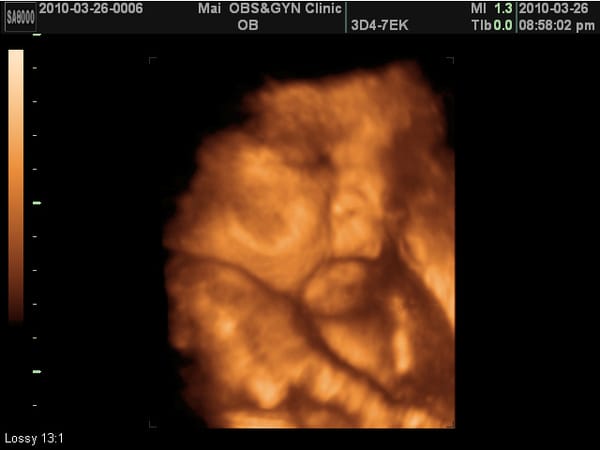

小老虎第九次產檢,驗尿ok,血壓………,母親體重65.9KG,兩周共增重1.2KG。 乙型鏈球菌檢驗正常。 小老虎上次產檢2500公克,這次2600多公克,這兩周吃的東西都長在媽媽身上。 血壓:112/54 心跳:………. 這次又看得到4D照了,相當有肉,臉頰有肉、鼻子有肉、嘴巴也很有肉、連胸部也擠出一團肉~~~ (但是這周 […]…

醫生說看起來像媽媽,像嗎? 我覺得臉胖胖的,鼻子扁扁的,嘴巴厚厚的耶~ 傅說:哪個小孩子不是長這樣?     小老虎第六次產檢,驗尿ok,血壓ok,母親體重64.5KG。 小老虎上次產檢913公克,這次1500多,這四周又胖了1.3KG,還OK。 血壓:94/47 頭28w,稍小。 小老虎的頭原本在我的右側,這次滾到左側來了,這一個月間她翻轉了一百八十度,難怪我的肚子老被她拿 […]…